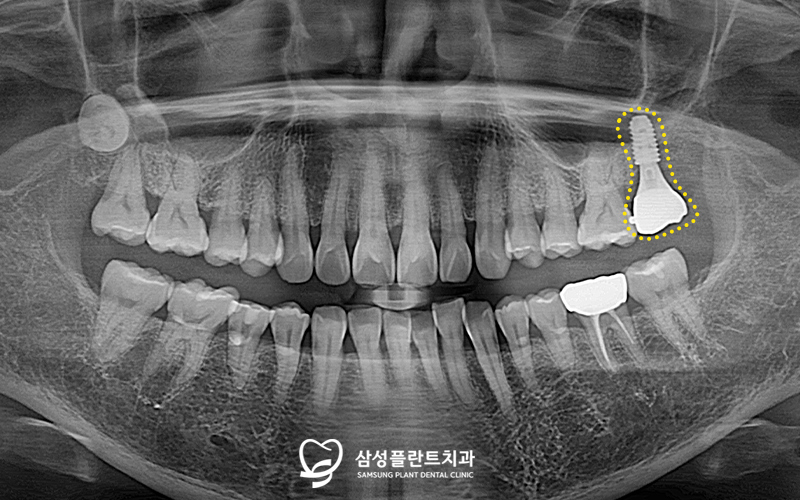

추후 임플란트가

뼈와 잘 결합되는 기간을 거친 뒤

2차 수술을 진행하였고,

이후 본을 떠서 임시치아를 장착해드렸습니다.

임시치아를 약 한달간 사용하면서

불편함이 없는지 확인한 후,

최종 보철물 셋팅까지 잘 마무리해드렸습니다!

환자분께서 한동안 왼쪽으로

아예 식사를 못하셨는데,

이제 불편함이 모두 사라졌다며

만족해하셨답니다.